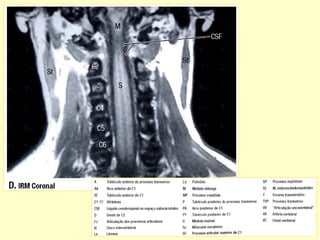

Fratura do axis – C2

ANATOMIA RADIOLÓGICA CERVICAL

Anatomia radiológica